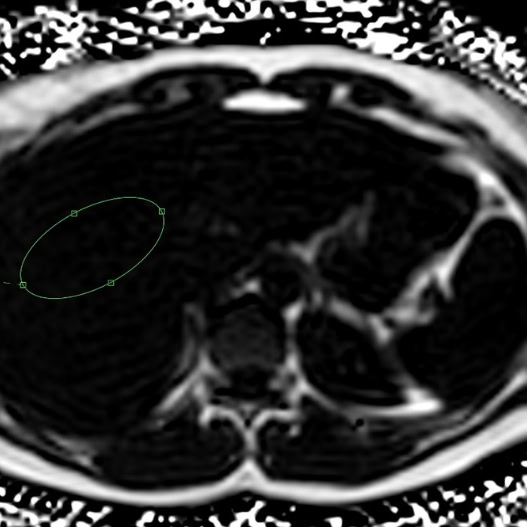

04.Advanced 3T MRI

Whole Body Scan

1 in 20 scans result in a potentially life-saving diagnosis

For unexplained symptoms, genetic and family history and a proactive health mindset.